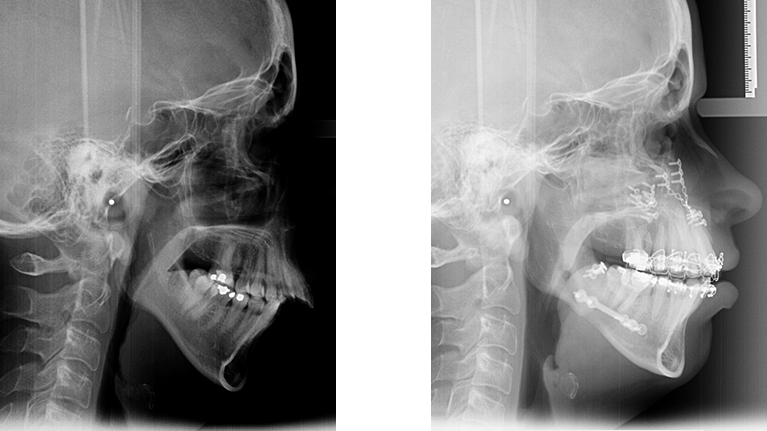

Person med overbid og vigende hage